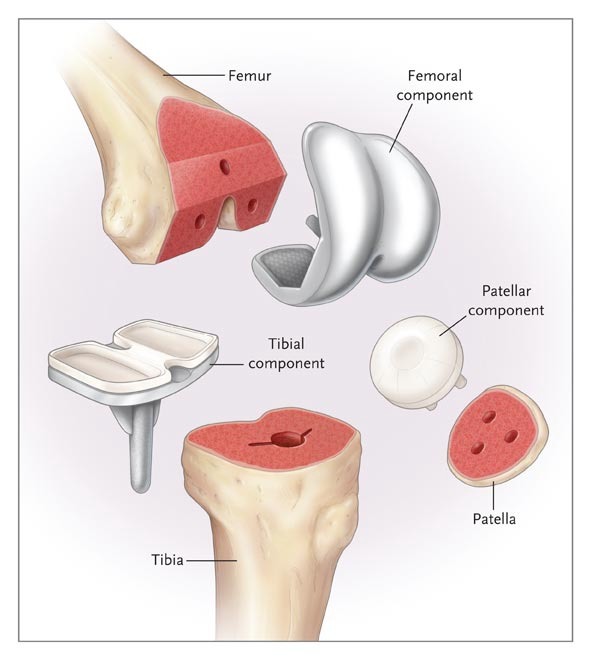

پروتزهای مفصل زانو :

علم طراحی و کارگذاری مفصل زانو علمی بسیار پیشرفته است که بر مبنای دو پیشرفت اساسی حاصل شده است.

یکی پیدا کردن موادی با حداقل اصطکاک سطحی. این مواد برای تمامی موارد تعویض مفصل عبارتند از پلیاتلین و فلز. پلیمر پلیاتلین هرچه دارای وزن مولکولی بیشتری باشد پایدار تر و در مقابل سائیدگی مقاوم تر است. فلز در مفاصل مختلف از فولاد ضد زنگ یا کروم کبالت و یا تیتانیوم استفاده میشود. در مفصل زانو از ترکیب پلیاتلین ultra-high density و کروم کبالت استفاده میشود. به این ترتیب که برای سطح مفصلی استخوان فمور(ران) از کومپوننت تمام فلزی استفاده میشود و برای سطح مفصلی استخوان تیبیا (ساق) از بخش فلزی برای اتصال به استخوان استفاده میشود که بر روی آن یک لایه حداقل 10 میلیمتری پلیاتلین قرار داده میشود که با کومپوننت فلزی فمور در تماس قرار میگیرد.

در کارگذاری معمول مفصل زانو در مورد مفصل پتلا (کشکک) پروتزی استفاده نشده و با اقدامات خاصی سطح مفصلی آن صاف و بدون درد میشود اما اگر قرار به تعویض سطح مفصلی آن باشد از کومپوننت پلیاتلینی استفاده میشود که در تماس با کومپوننت فلزی فمور قرار میگیرد.